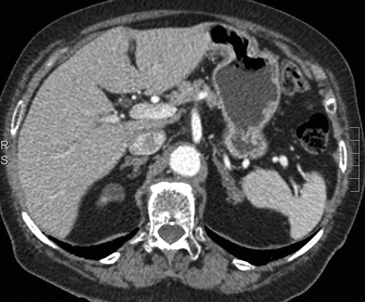

En la TC no contrastada las glándulas suprarrenales normales son homogéneas y simétricas, con una densidad muy similar a la del parénquima renal adyacente (Figura 1 a). Con un medio de contraste ev la glándula suprarrenal se opacifica en forma homogénea, similar al hígado o al bazo (Figura 1 b). Si la cantidad de tejido adiposo retroperitoneal es abundante las glándulas suprarrenales pueden aparecer enteramente rodeadas por grasa y su delimitación es más fácil (Figura 2 a); lo inverso ocurre en pacientes muy delgados con escasa grasa retroperitoneal (Figura 2 b). En RM, en secuencias ponderadas en T1 y T2 convencionales tienen una intensidad de señal homogénea, hipointensa respecto de la grasa adyacente e iso o hipointensa con respecto del parénquima hepático (Figura 3 a y b). En los cortes coronales se aprecia mejor la forma y la posición de las glándulas suprarrenales (Figura 3 c).

Figura 1. Glándula suprarrenal normal en tomografía computada. Cortes axiales de tomografía computada, donde se identifica la morfología normal de la glándula suprarrenal derecha (flecha) en fase no contrastada (a), y tras el uso de medio de contraste endovenoso (b).